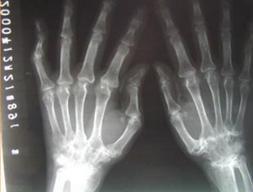

(图:从X光上可以看出程先生手部轻微尺偏变形)

根据程先生的描述,主任首先对程先生进行了全身的检查,程先生手部出现轻微尺偏,脚部关节变形较手部严重;膝关节肿胀并且关节腔有积水;手臂抬起困难,抬起会产生疼痛感,初步怀疑肩部关节受损;其他关节良好。